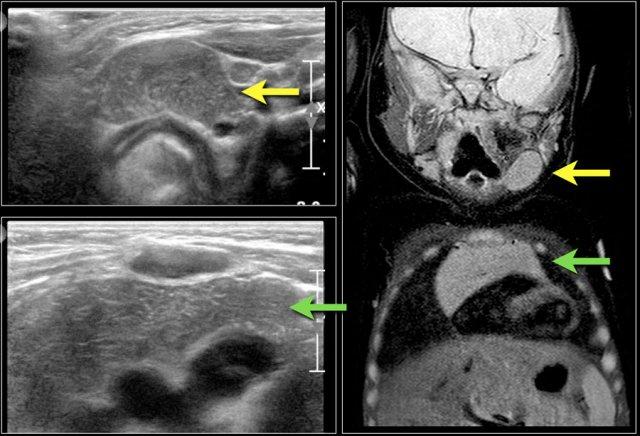

Đây là hình ảnh siêu âm của một u mạch bạch huyết điển hình.

MRI được thực hiện vì sự lan rộng của tổn thương chưa được xác định rõ ràng.

Here the T2-weighted image of the same patient.

Trên ảnh T1, nội dung bên trong có cường độ tín hiệu thay đổi, tùy thuộc vào hàm lượng protein hoặc máu.

Thường có cường độ tín hiệu cao trên ảnh T2.

T1 có tiêm thuốc tương phản có thể cho thấy sự ngấm thuốc của thành nang.

Đây là hình ảnh siêu âm của một bé gái sáu tuổi với tình trạng sưng đột ngột ở cổ bên trái.

Có nhiều nang nhỏ không có âm vang và một nang lớn chứa các âm vang bên trong, có thể là kết quả của xuất huyết trong một u bạch huyết mạch có sẵn từ trước.

Một bé trai 3 tuổi đột ngột xuất hiện khối u vùng trên xương đòn.

Ultrasound showed a lesion with echogenic debris.

A hemorrhage in a preexisting lymphangioma was suspected.

Continue with the MRI.

Hình ảnh T1-weighted cho thấy một tổn thương tăng tín hiệu nhẹ với mức độ dịch-dịch (mũi tên).

Sau khi tiêm gadolinium, có sự tăng tín hiệu của thành nang.

The lesion subsided with conservative therapy.